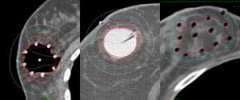

Partial breast irradiation (PBI) (fig 2&3)

- External Beam

- Balloon based implant

- Interstitial needle implant

- Intraoperative (IORT) – One treatment One day